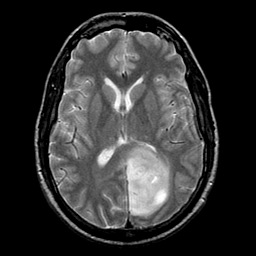

Glioma overlay -- Slice #15

[Home][Help][Clinical] Slice 15